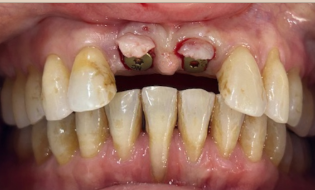

Before

- When patient was a teenager, both #8/#9 tooth fell out of socket

- Dentists did root canals on both teeth extraorally and re-inserted into socket

- #8 root horizontal fracture

- Both u1s showed root resorption

- HTE: #8 horizontal root fracture at bone level

- Failed root coverage surgery on #25